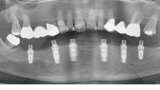

Počítačem asistované, šablonou se řídící okamžité zavedení a zatížení implantátu v dolní čelisti